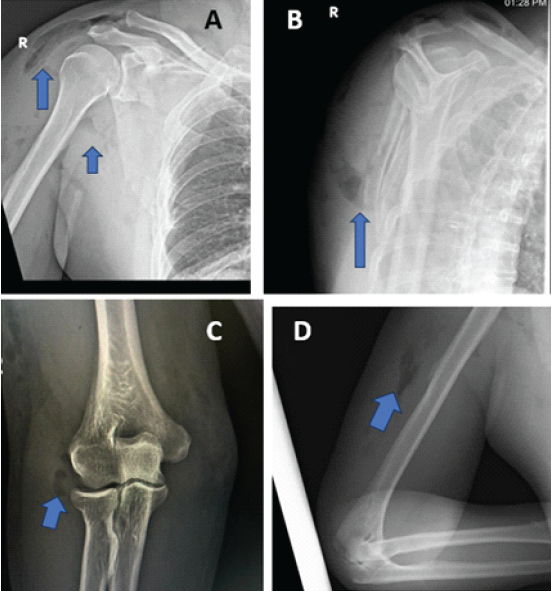

Anteroposterior and lateral radiographs of the right shoulder and elbow showed linear radiolucent streaks within the soft tissues, consistent with SE (Fig. 2). An extra-articular fracture of the scapular body was also noted. A chest radiograph revealed no evidence of pneumothorax, hemothorax, rib fractures, or mediastinal shift.

Figure 2: Plain radiographs of the right upper limb. (a) Anteroposterior (AP) view of the shoulder showing air lucencies in the soft tissue planes around the scapula and proximal arm (blue arrows), suggestive of subcutaneous emphysema. (b) Scapular Y-view demonstrating subcutaneous air in the axillary region (blue arrow). (c) AP view of the elbow showing air shadows in the subcutaneous tissue overlying the distal humerus (blue arrow). (d) Lateral view of the elbow confirming subcutaneous emphysema in the posterior soft tissue planes (blue arrow).